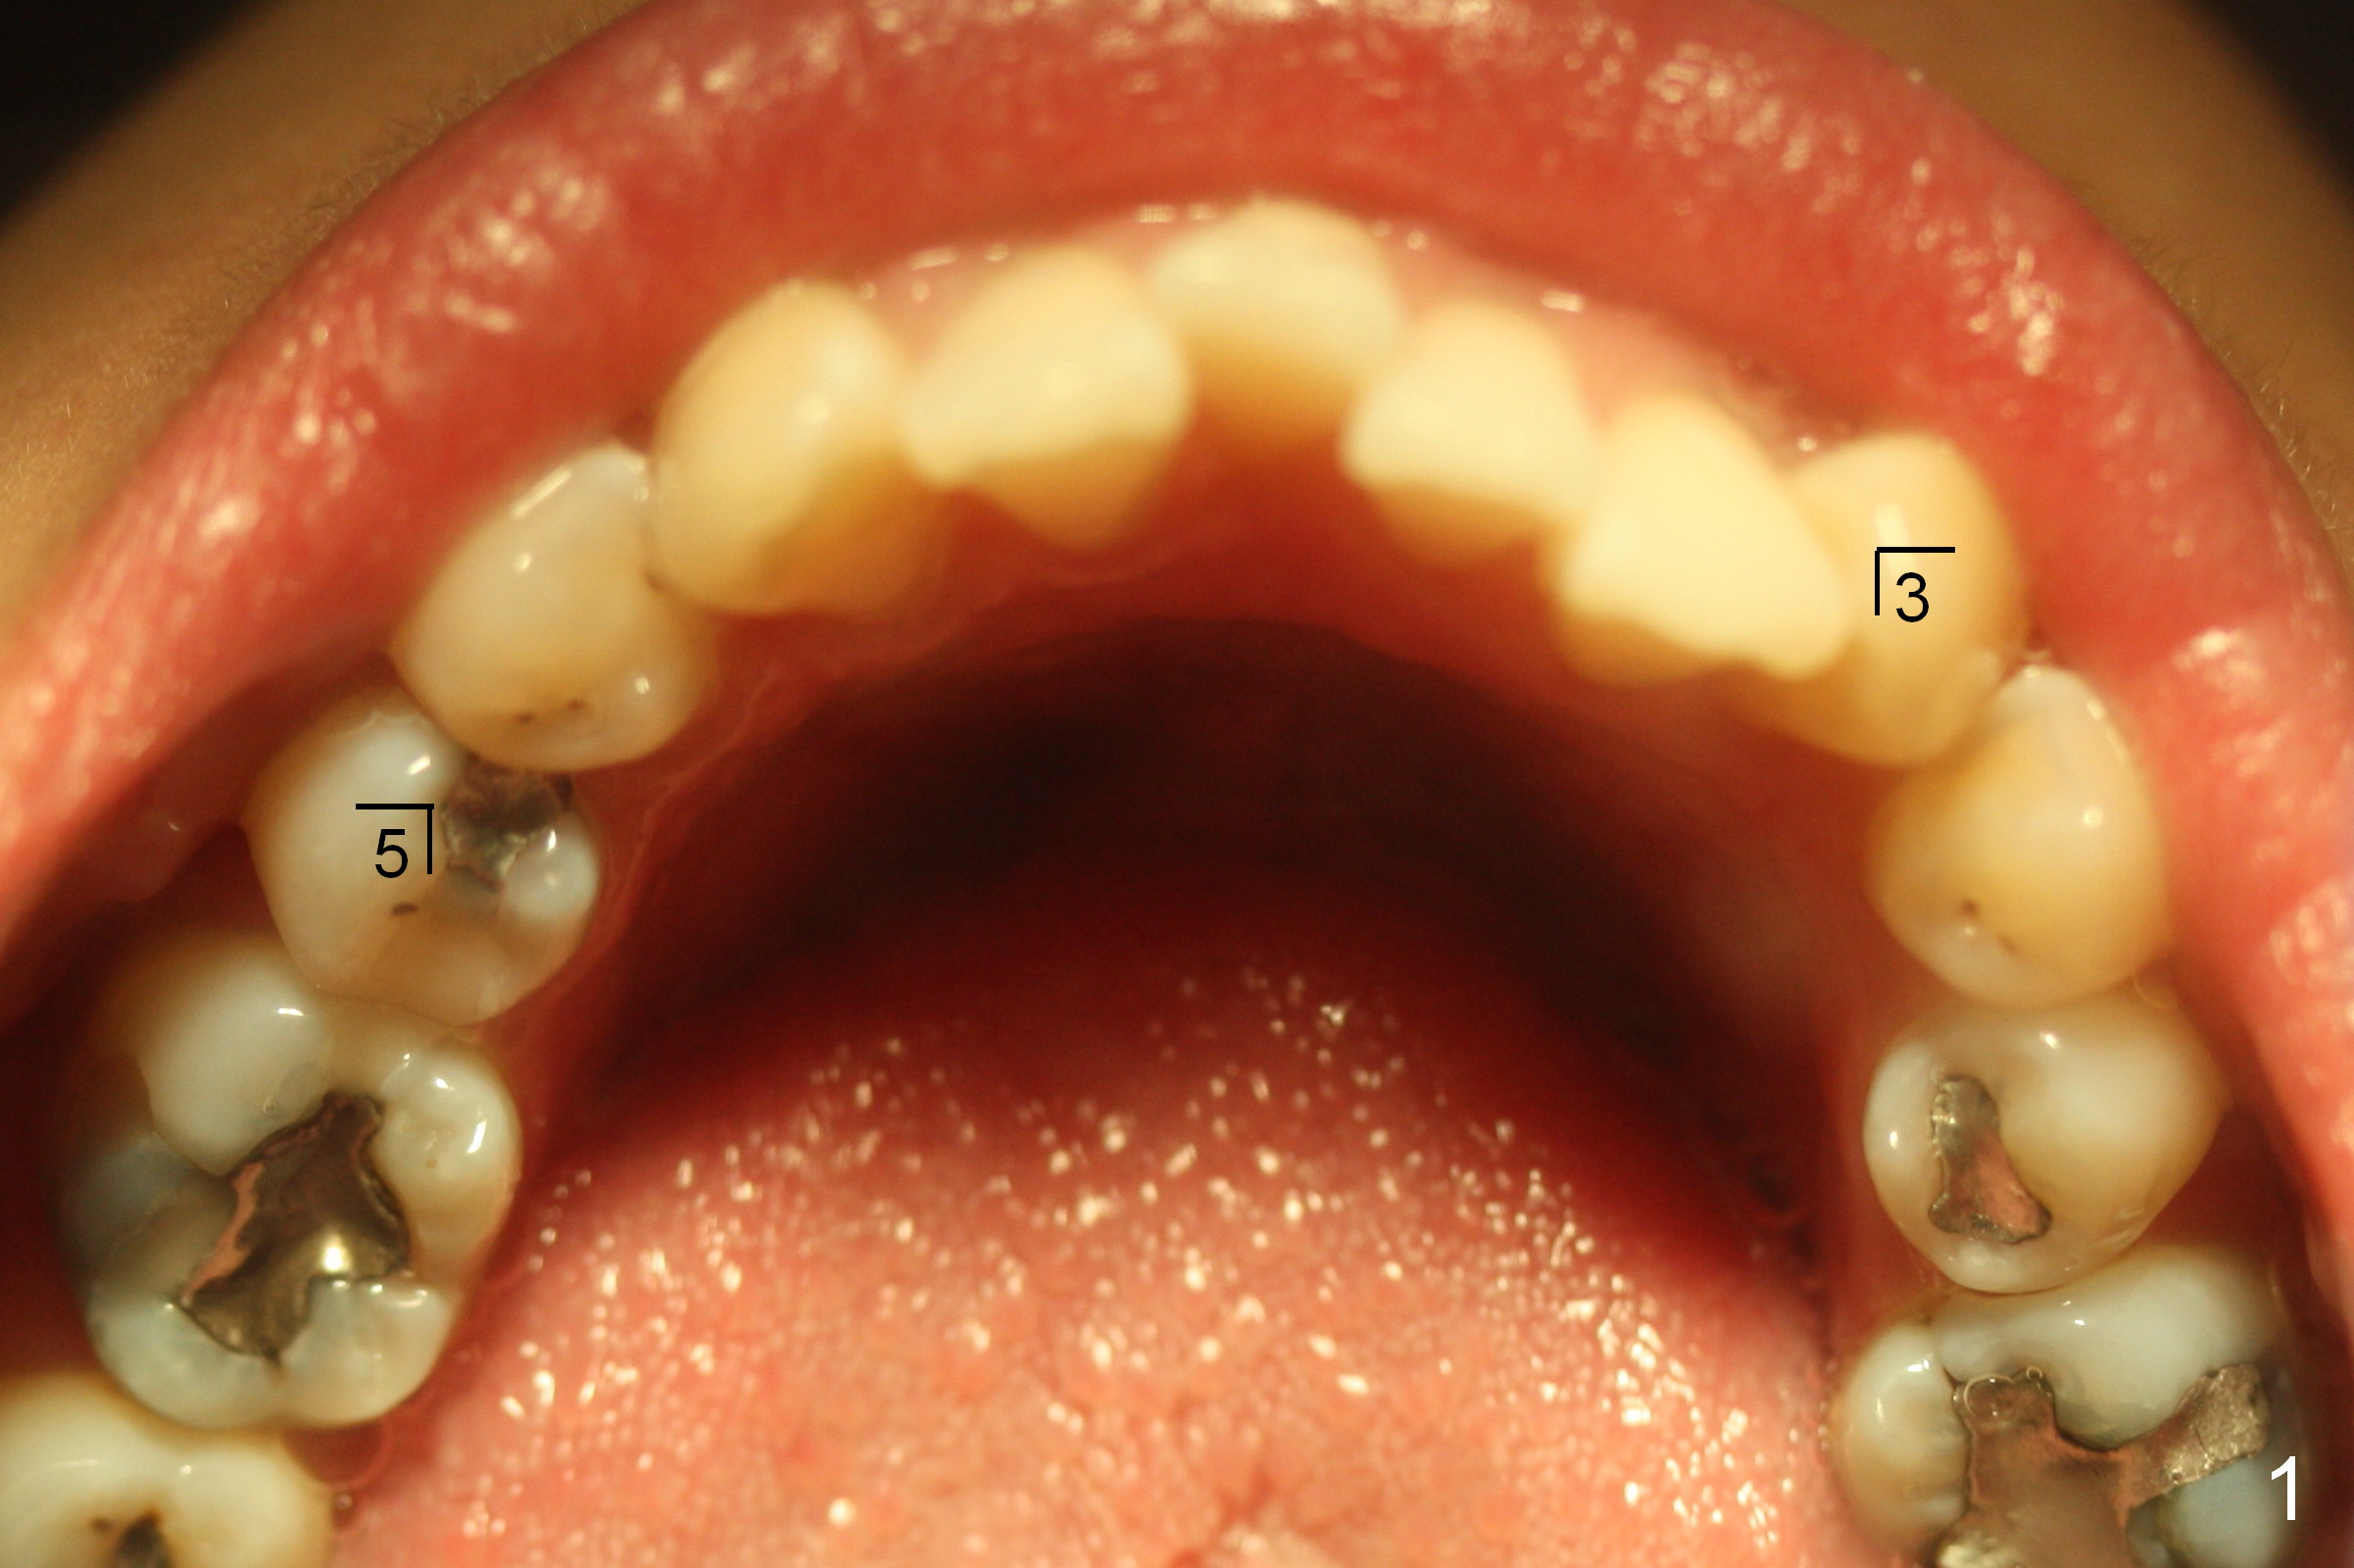

The lower 4s are expected to be extracted. On the day of surgery, LR 5 is found to have been heavily restored (MO amalgam, DO composite, Fig.1); the prognosis is less favorable than LR 4. So the former is extracted (Fig.2).

On the other side, the canine area is crowded (Fig.1: 3). Therefore the lower left 1st bicuspid is extracted (Fig.2). Fig.2 is taken on the day of banding (2 weeks post extraction). A Niti wire (.014") is used. According to model surgery, the anterior teeth are to be distalized (Fig.2 arrows).